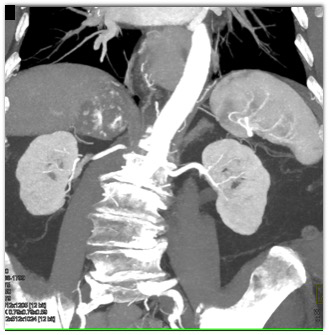

The best diagnosis in this patient with an incidental finding is

adrenal adenoma

adrenal pheochromocytoma

adrenal myelolipoma

adrenal carcinoma